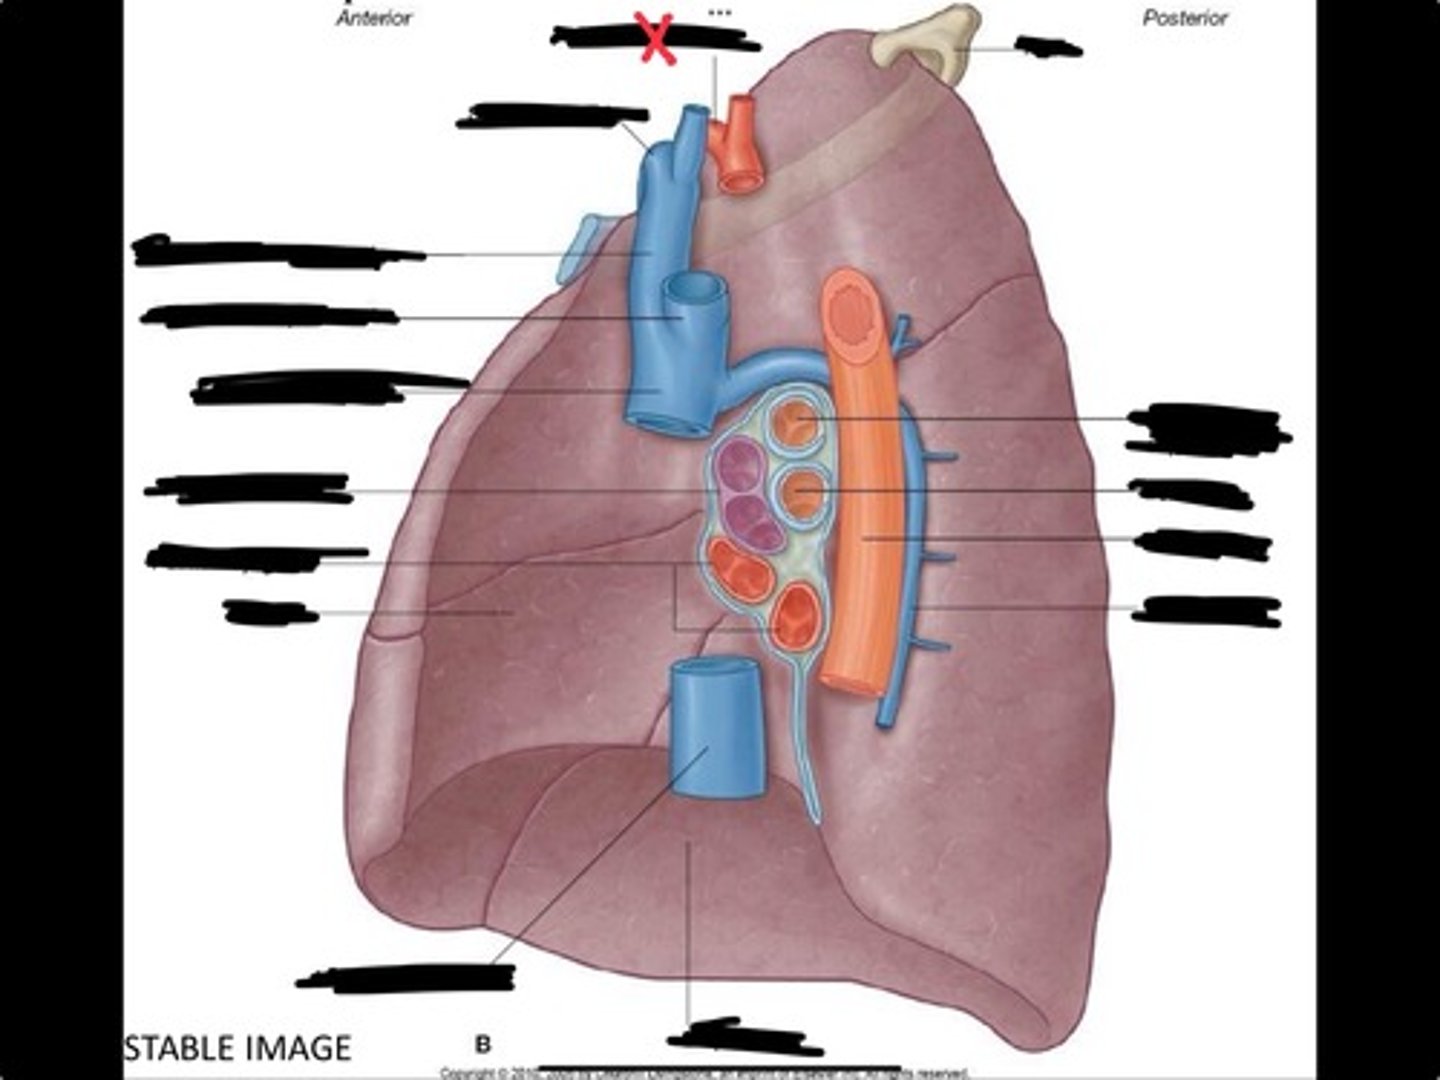

Rib 1

Pulmonary artery

Bronchus to superior lobe

Pulmonary veins